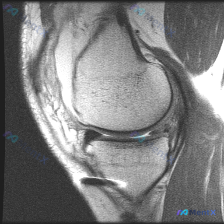

看到一份膝关节MRI的读片需求,核心问题是半月板异常,我整理了完整的分析思路,分享给大家。 病例影像基础信息 这是一张膝关节矢状位T2加权MRI,观察层面为膝关节外侧室,可显示股骨外侧髁、胫骨外侧平台、外侧半月板体部结构。 系统性影像学发现 1. 骨骼与关节软骨:股骨、胫骨骨皮质信号正常,骨髓无异常...